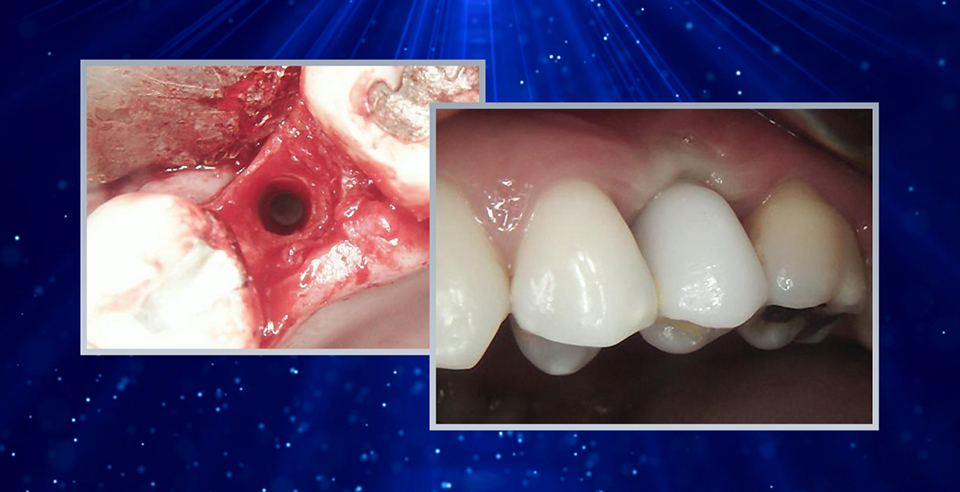

REPLACEMENT THE CENTRAL ELEMENT WITH AN IMPLANT - CASE BY DR CARMY MICHAEL